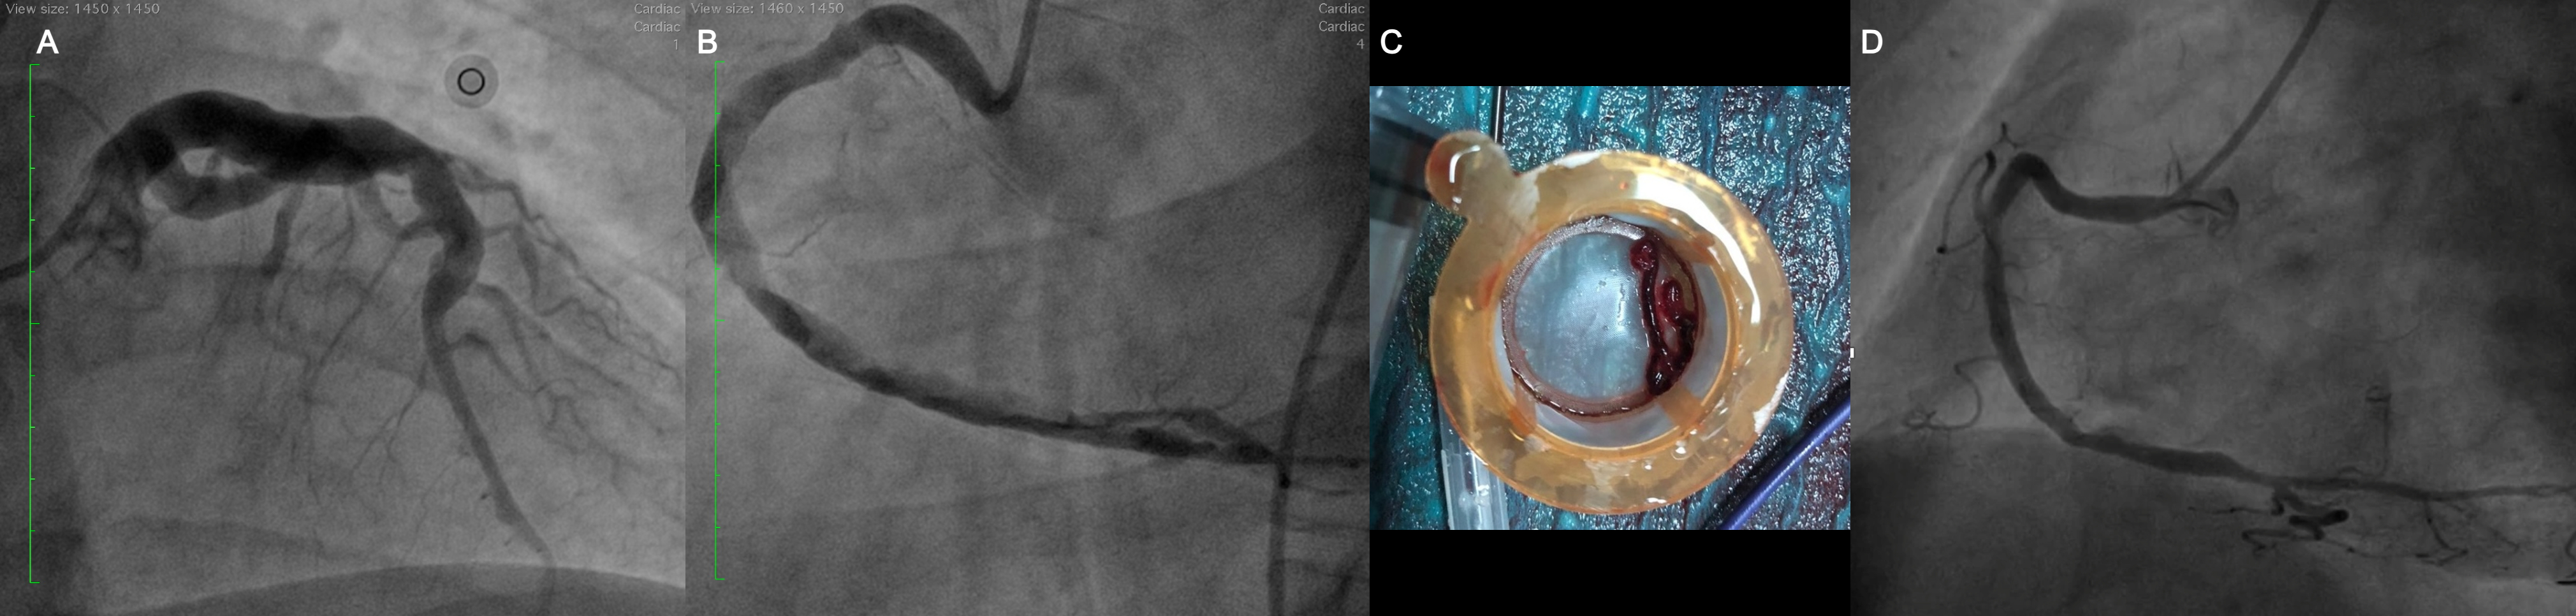

A 33-year-old man with Behçet's disease (BD) presented with new retrosternal chest pain and was transferred for primary percutaneous coronary intervention (PCI) due to inferior ST-segment elevation myocardial infarction. Coronary angiography showed aneurysmal dilation of the left coronary system and ectasia of the right coronary artery (RCA), which had a high thrombus burden and slow flow.

Thrombus aspiration was performed with an Export Advance aspiration catheter (Medtronic), and a long red thrombus was removed. Intracoronary tirofiban was administered from the aspiration catheter, but no stent was placed due to the patient’s age, aneurysmatic arteries, and a potential relationship with BD. In the cardiac intensive care unit, intravenous tirofiban and a heparin drip were used to achieve a target activated clotting time of 250 seconds. Rheumatology consultation confirmed active BD, leading to high-dose pulse steroids and cyclophosphamide treatment.

The patient was closely monitored for 2 weeks and received triple therapy with aspirin, clopidogrel, and apixaban for 1 month. Follow-up angiography at the third month showed regression of his RCA ectasia with distal Thrombus in Myocardial Infarction-3 flow. Echocardiography demonstrated a left ventricular ejection fraction of 60%, and the patient has reported no symptoms since the event.